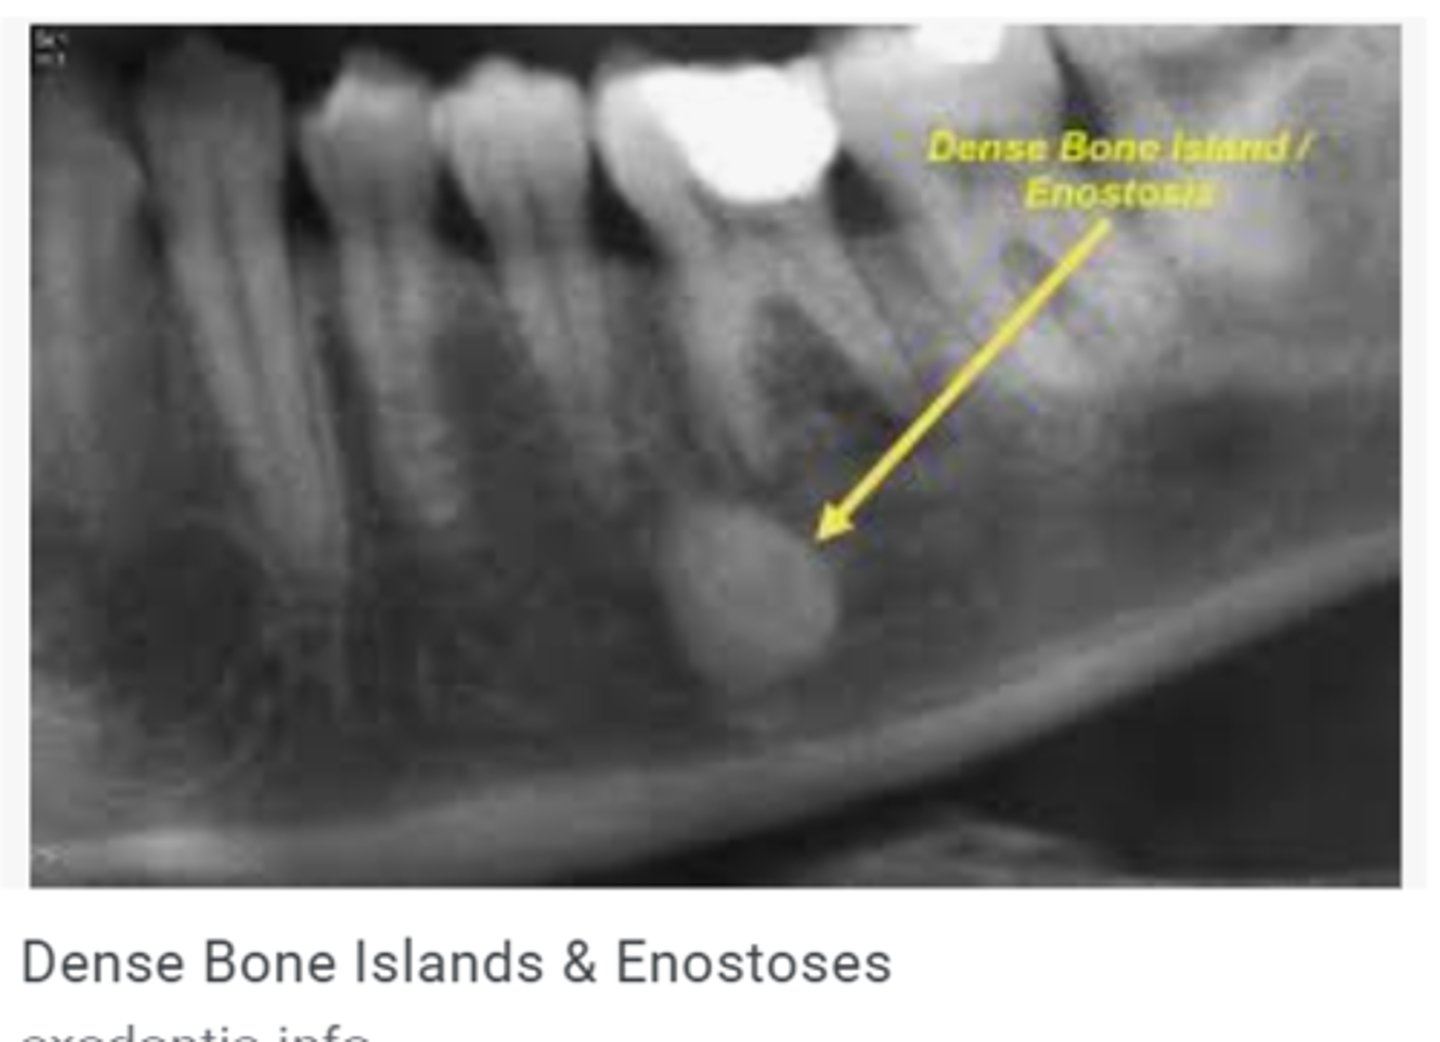

What is enostosis?

Dense bone island

What is the most common finding in radiographs?

Enostosis (one bone island)